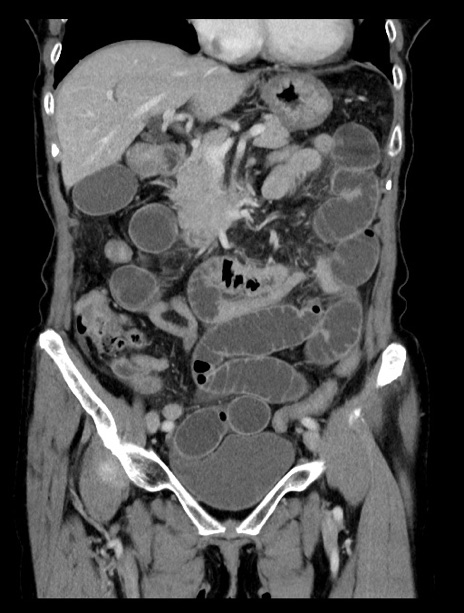

症例23(冠状断像)

【症例】70歳代女性

【主訴】下腹部痛・嘔吐

【現病歴】2日前より腹痛あり。昨日嘔吐あり。症状改善しないため来院。

【既往歴】胃GISTに対して胃部分切除後。

【身体所見】BT 37.1℃、BP 128/77mmHg、腹部:平坦・軟、下腹部に圧痛あり。

【データ】WBC 10200、CRP 0.31